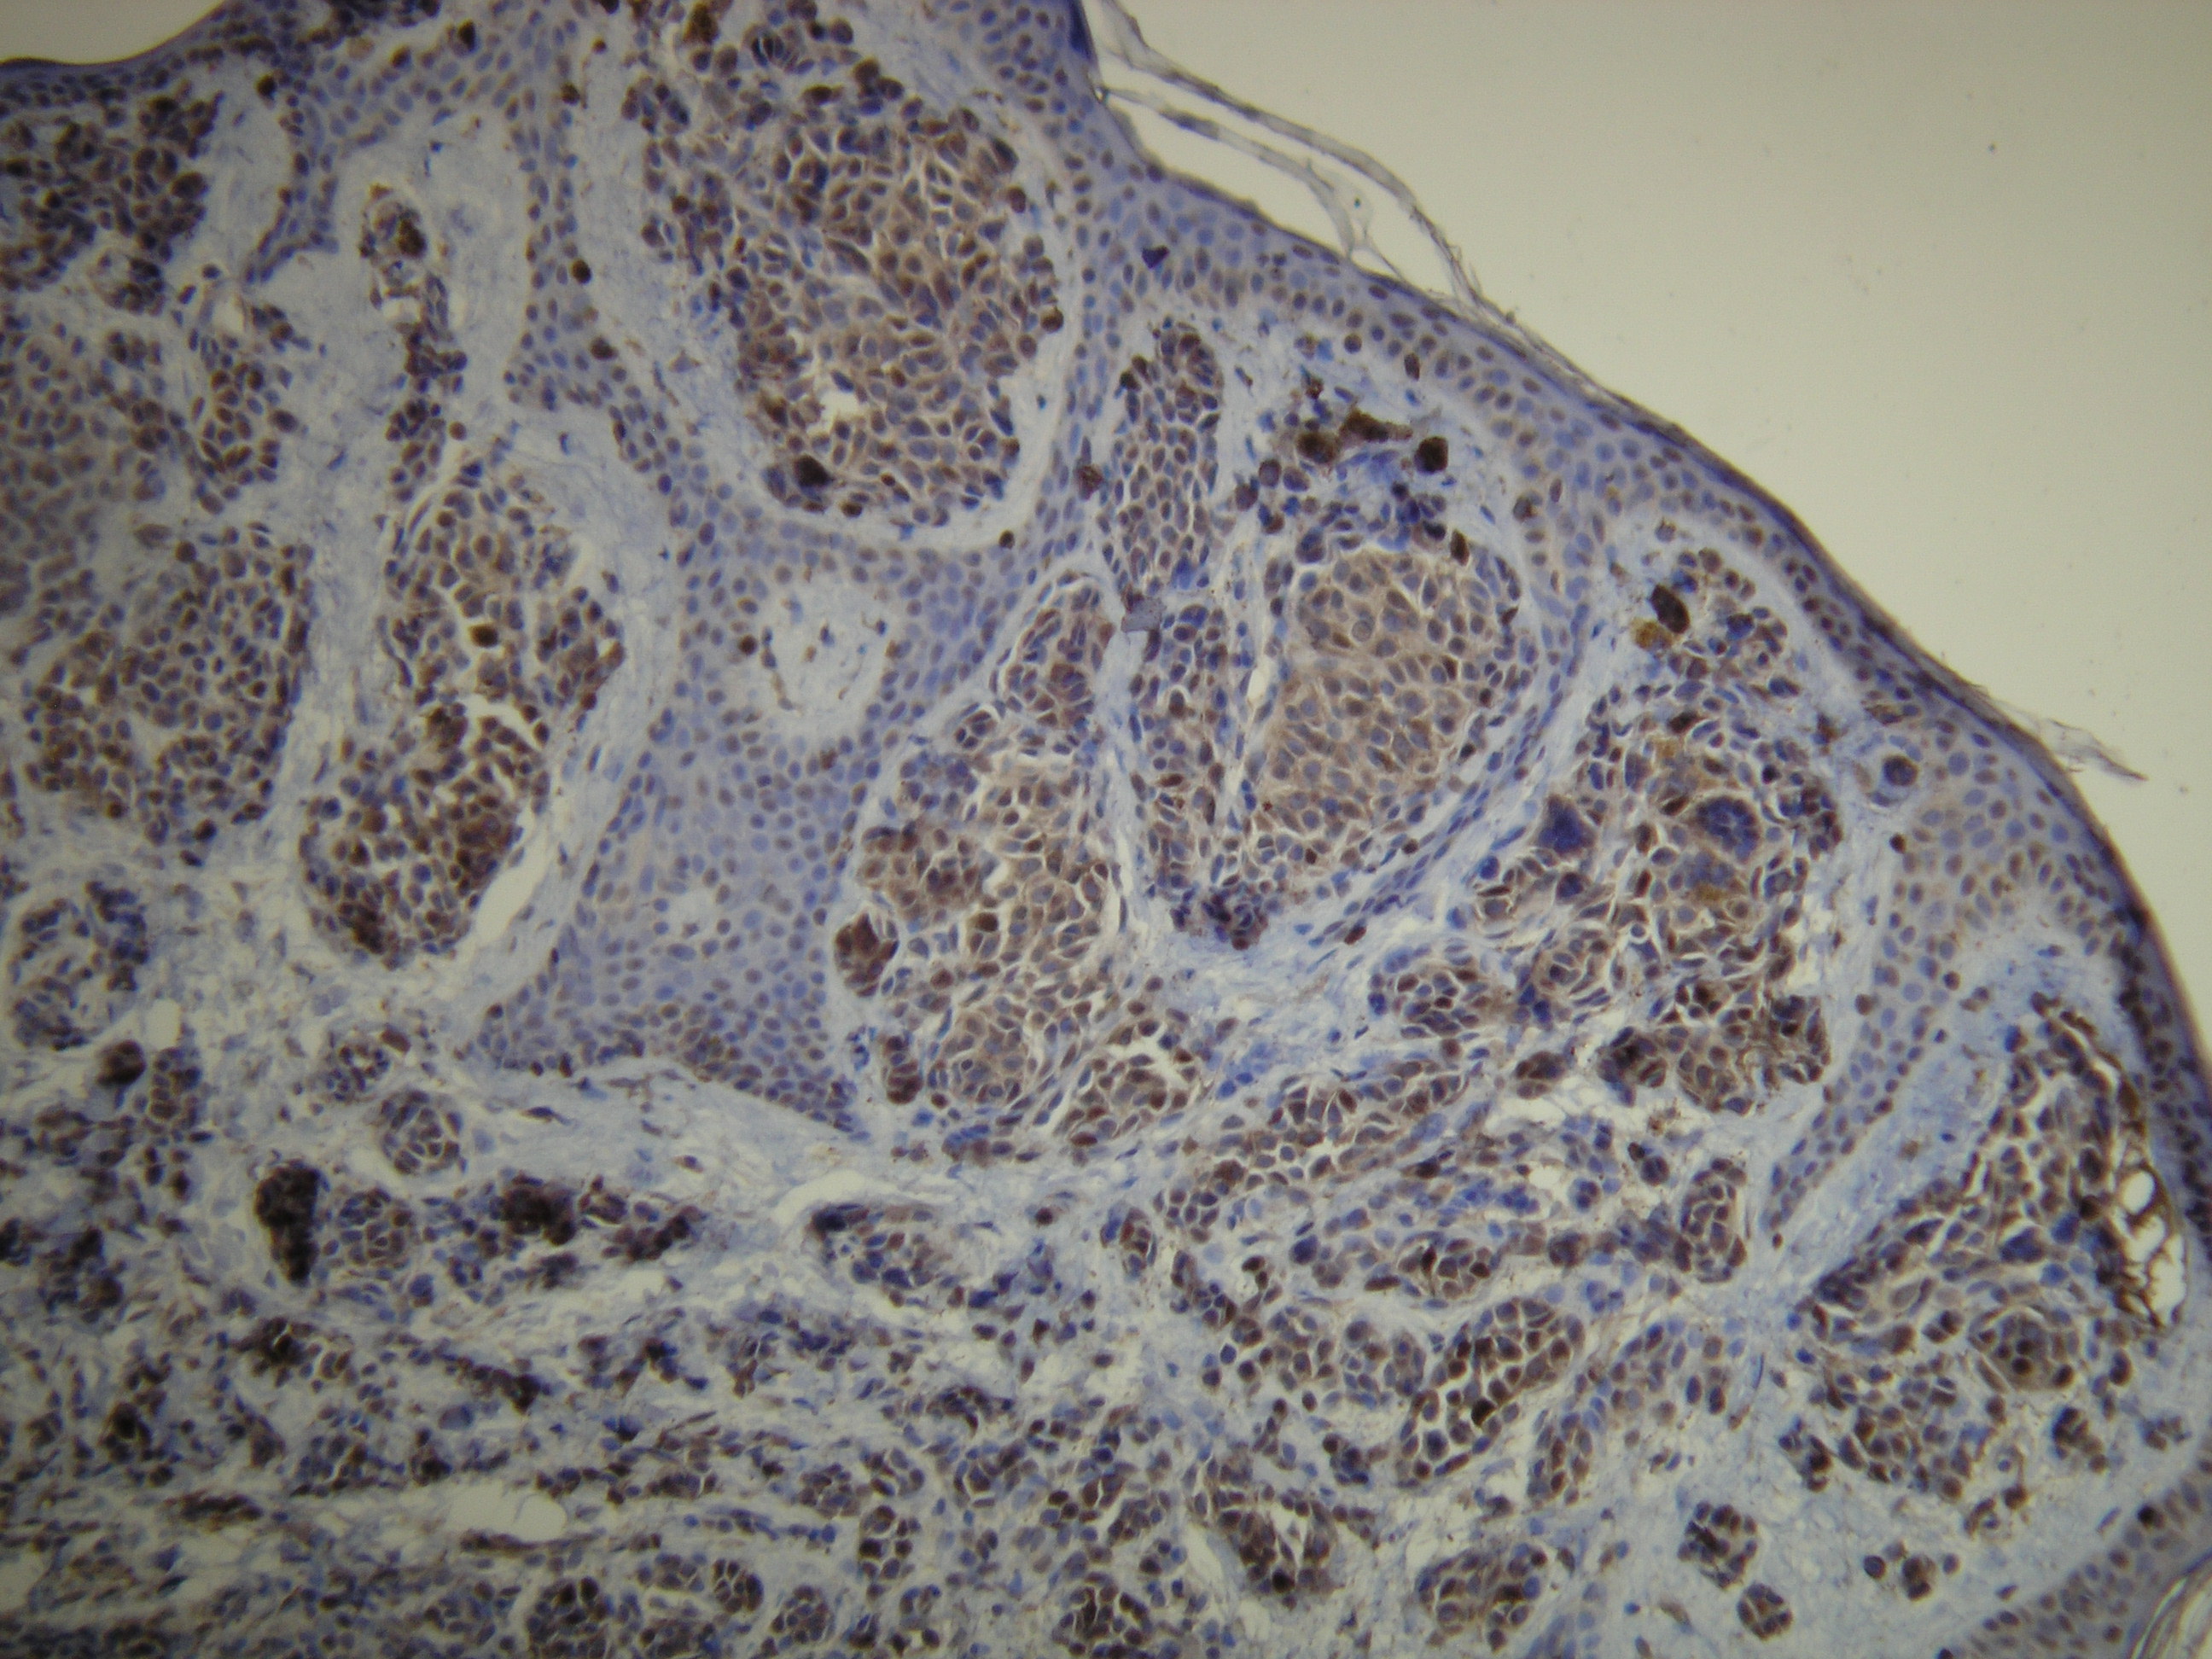

Anti-S-100

Peptid derivovaný z N-koncovej sekvencie ľudského S100-A1 proteínu. Protilátka rozpoznáva epitop umiestnený medzi Val55 – Glu74.

IHC-P, riedenie 1:100

db055